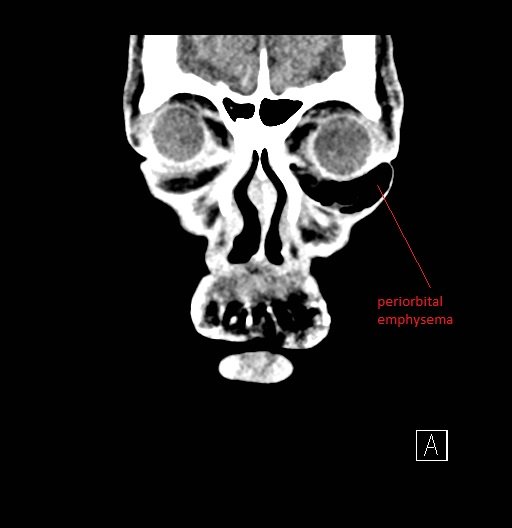

Physical exam showed marked left palpebral subcutaneous crepitus, as well as bulbar and palpebral conjunctival bulging. Visual acuity was normal with intact extraocular movements, and normal pupillary exam. Computed tomography (CT) imaging of the face was obtained and revealed multiple displaced fractures involving the left orbital floor and zygomatic arch associated with moderate periorbital and postseptal extraconal gas, resulting in orbital proptosis.